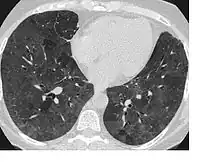

CT image showing diffuse GGOs throughout both lungs. An abscess is also noted in the right lung (screen left). - Adenocarcinoma in situ of the lung

The diffuse pattern typically refers to GGOs in multiple lobes of one or both lungs. Broadly, a diffuse pattern of GGO can be caused by displacement of air with fluid, inflammatory debris, or fibrosis. Cardiogenic pulmonary edema and ARDS are common causes of a fluid-filled lung. Diffuse alveolar hemorrhage is a rarer cause of diffuse GGO seen in some types of vasculitis, autoimmune conditions, and bleeding disorders.[6]

Inflammation and fibrosis can also cause diffuse GGOs. Pneumocystis pneumonia, an infection typically seen in immunocompromised (e.g. patients with AIDS) or immunosuppressed individuals, is a classic cause of diffuse GGOs. Many viral pneumonias and idiopathic interstitial pneumonias can also lead to a diffuse GGO pattern. Radiation pneumonitis, a side effect of pulmonary radiation therapy, can lead to pulmonary fibrosis and diffuse GGOs.[6]